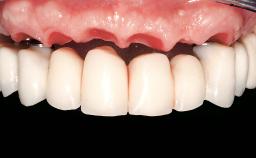

| Jaw | Maxilla and Mandible |

| # of Teeth | 9 |